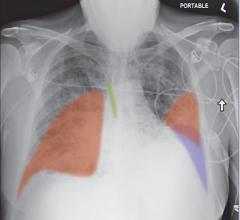

Lunit, a leading medical AI provider, announced that the U.S. Food and Drug Administration (FDA) 510(k) has cleared its ...